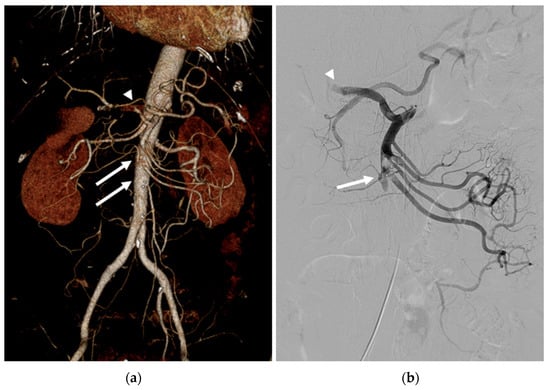

The CT revealed a segmental thrombus in the SMA, a focal thrombus in the common hepatic artery (CHA), and splenic infarction. A hepaticomesenteric common trunk, a rare anatomical variant of the hepatic artery, was observed. (Figure 1a) Moreover, no signs of peritonitis or bowel ischemia were observed. Because his symptoms started three hours previously without peritoneal irritation, the emergency physician referred the patient to us for EVT.

A 6F sheath was introduced into the right common femoral artery, and the SMA was selectively catheterized using a 5 Fr RH catheter (Cook Medical, Bloomington, IN, USA). Angiography revealed proximal SMA and CHA occlusions (Figure 1b).

Figure 1. (a) Three-dimensional volume-rendered image of abdominal CT angiography revealed a segmental thrombus in the proximal SMA (arrows) and a focal thrombus in the CHA (arrowhead). A hepaticomesenteric common trunk was also observed. (b) Initial angiography revealed occlusion of the proximal SMA (arrow) and the CHA (arrowhead).